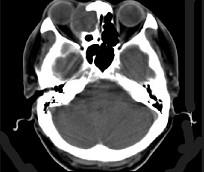

问题 女性,38岁,右侧眼球运动障碍伴眼球突出4个多月,CT扫描如图,请选择正确的描述和答案 ( )

选项 A、考虑为右侧筛窦黏液囊肿 B、考虑为筛窦癌 C、囊性肿块向右侧眼眶内突入,压迫内直肌 D、右侧眶内壁呈受压变薄、断裂 E、右侧筛窦内可见囊性肿块影,边缘光整

答案 ACDE